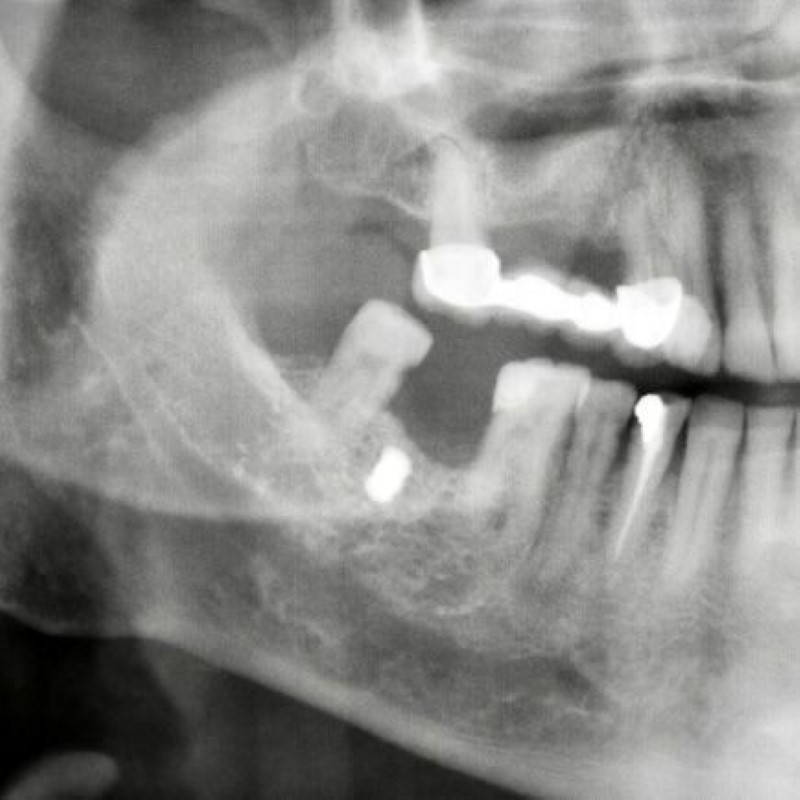

Hastaneye müracaat etmeyen Faik Akın’ın yüzüne gelen demir parçalardan biri damağında yıllarca kaldı. Diş tedavisi için hastaneye gelen Faik Akın’ı muayene eden Ağız ve Çene Cerrahı Dr. Öğretim Üyesi Yakup Gülnahar, hastanın röntgen filmine bakınca damağında bir nesne olduğunu belirledi.

Ameliyatı gerçekleştiren Dr. Yakup Gülnahar, “Hastanın muayenesinde rutin röntgen filmi istedik. Röntgenlerde hastanın yanağında bir cisim olduğunu anladım. Kendisine daha önce implant yaptırıp yaptırmadığını sordum. Kendisi implant yaptırmadığını söyledi. Bu sefer hastanın yanağında ne olabilir diye düşünürken hastanın 15 yıl önce benzinli odun testeresi ile çalışırken testerenin zincirinin koptuğunu ve etrafa saçılan parçalardan yanağına isabet ettiğini öğrendik. Hastamızı ameliyata aldık ve yanağındaki demir parçayı çıkardık. Hastamız da şu an gayet iyi bir durumda” şeklinde konuştu.